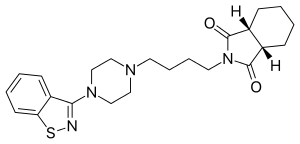

| Formula | C23H30N4O2S |

| Molar mass | 426.58 g·mol−1 |